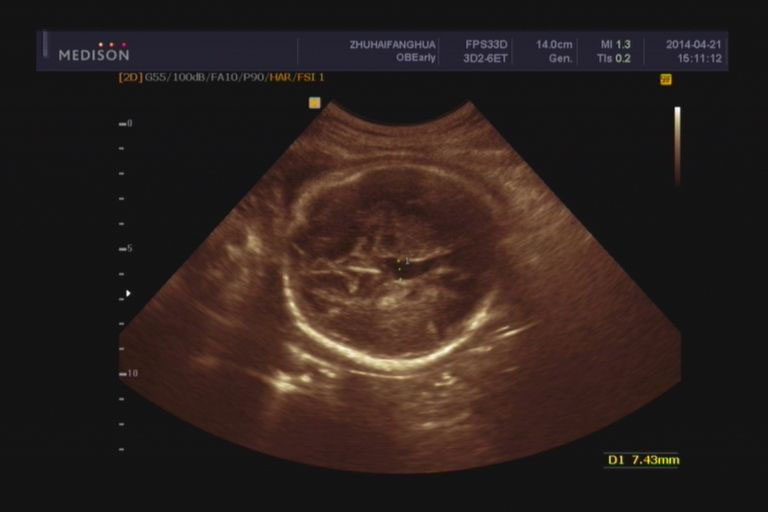

首先要明确,同样诊断为脑积水,脑室大小还是差别挺大的。在产前检查中,只要侧脑室后角扩张超出1.5cm,就会打脑积水的诊断。如果脑室确实显得非常大,把大脑皮层都挤压得很薄了,那没什么好犹豫了,绝对不能要了。但如果刚刚达到这个标准或者稍稍超出,就要认真评估一下了。

孕期有些扩张可能是一过性的,如果在孕中期开始发现,可以先动态观察,看看有没有变化。如果一直稳定,几次B超检查没有随着孕期异常增大(随着胎儿生长发育同步增大的除外),那么可以继续妊娠。如果明显增大,建议做个胎儿磁共振。

有没有局部的囊肿压迫。判断脑室扩张是整个脑室均衡扩张还是局部一个角发生扩张?局部囊肿压迫造成的扩张,可以考虑继续妊娠,但重点要观察囊肿有没有继续增大。